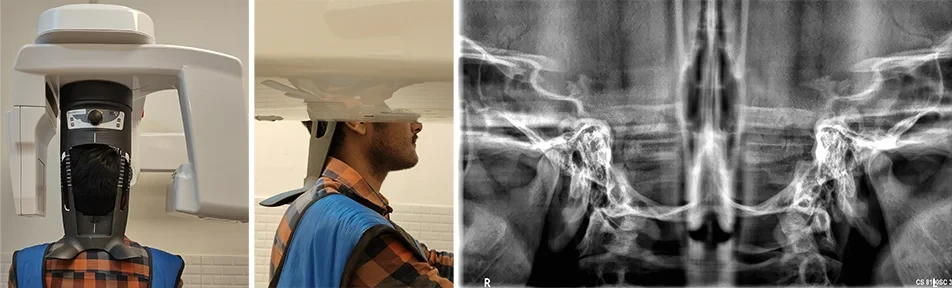

Bolstered by state-of-the-art technology like CBCT, the Radiology section ensures precision in diagnostic imaging.

Oral Medicine & Radiology is concerned with diagnosis and medical management of diseases specific to the oral & maxillofacial structures, management of oral manifestations of systemic diseases, management of behavioral disorders, and dental treatment of medically compromised patients. It deals with the diagnostic intraoral and extraoral imaging of maxillofacial structures by both conventional and digital methods. It further includes Forensic Odontology and also promotes tobacco cessation.

Oral Radiologists deals with the diagnostic intraoral and extraoral imaging of maxillofacial structures which includes both conventional and digital imaging where as a General Radiologists deals with the imaging of the rest of the body with the same modalities.